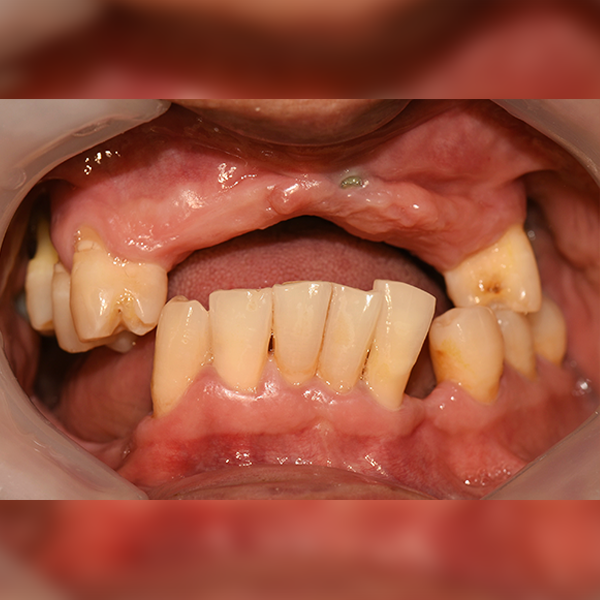

Trường hợp 160. Jin*young, 50 tuổi, 2020-02-06 / 2020-12-11

Before Before

After After